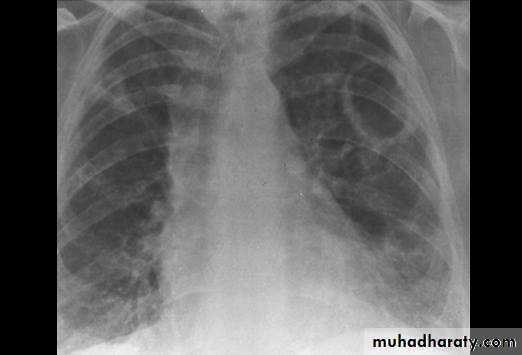

Radiopaque hemi-thoraxPneumothorax (air in pleural space )

Signs

Loss of vascular markings at the outer parts of lung fieldsDemarcating pleural line between the lung & vessels lacking area.

Well demarcating of the scapula

Epsilateral lung collapse

Tension pneumothorax

Emergency condition

Pressure effect on the mediastinum & major vessels

Treatment by chest tubes